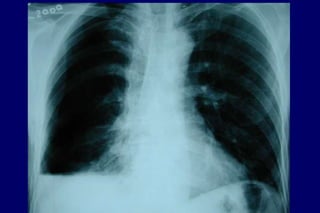

Radiografia

de tórax

Excluir outras

doenças

Bolhas

Hiperinsuflação

DIAGNÓSTICO História Exame físico Normal / quase Hiperinsuflação Murmúrio vesicular diminuído Sinaisde cor pulmonale mMRC-CAT Radiografia de tórax Excluir outras doenças Bolhas Hiperinsuflação Tabagismo Tosse Dispnéia Sibilos Exposição